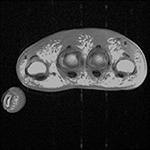

Figure 15 Figure 16 Figure 17 Figure 18A

MRI motion artifact MRI pulsation artifact Wraparound artifact Truncation artifact

Pulsation Artifact. Axial T2-weighted fat-saturated MR image of the pelvis demonstrates femoral artery pulsation resulting in ghost images (arrowheads) obscuring the anterior labra and simulating femoral head lesions bilaterally.